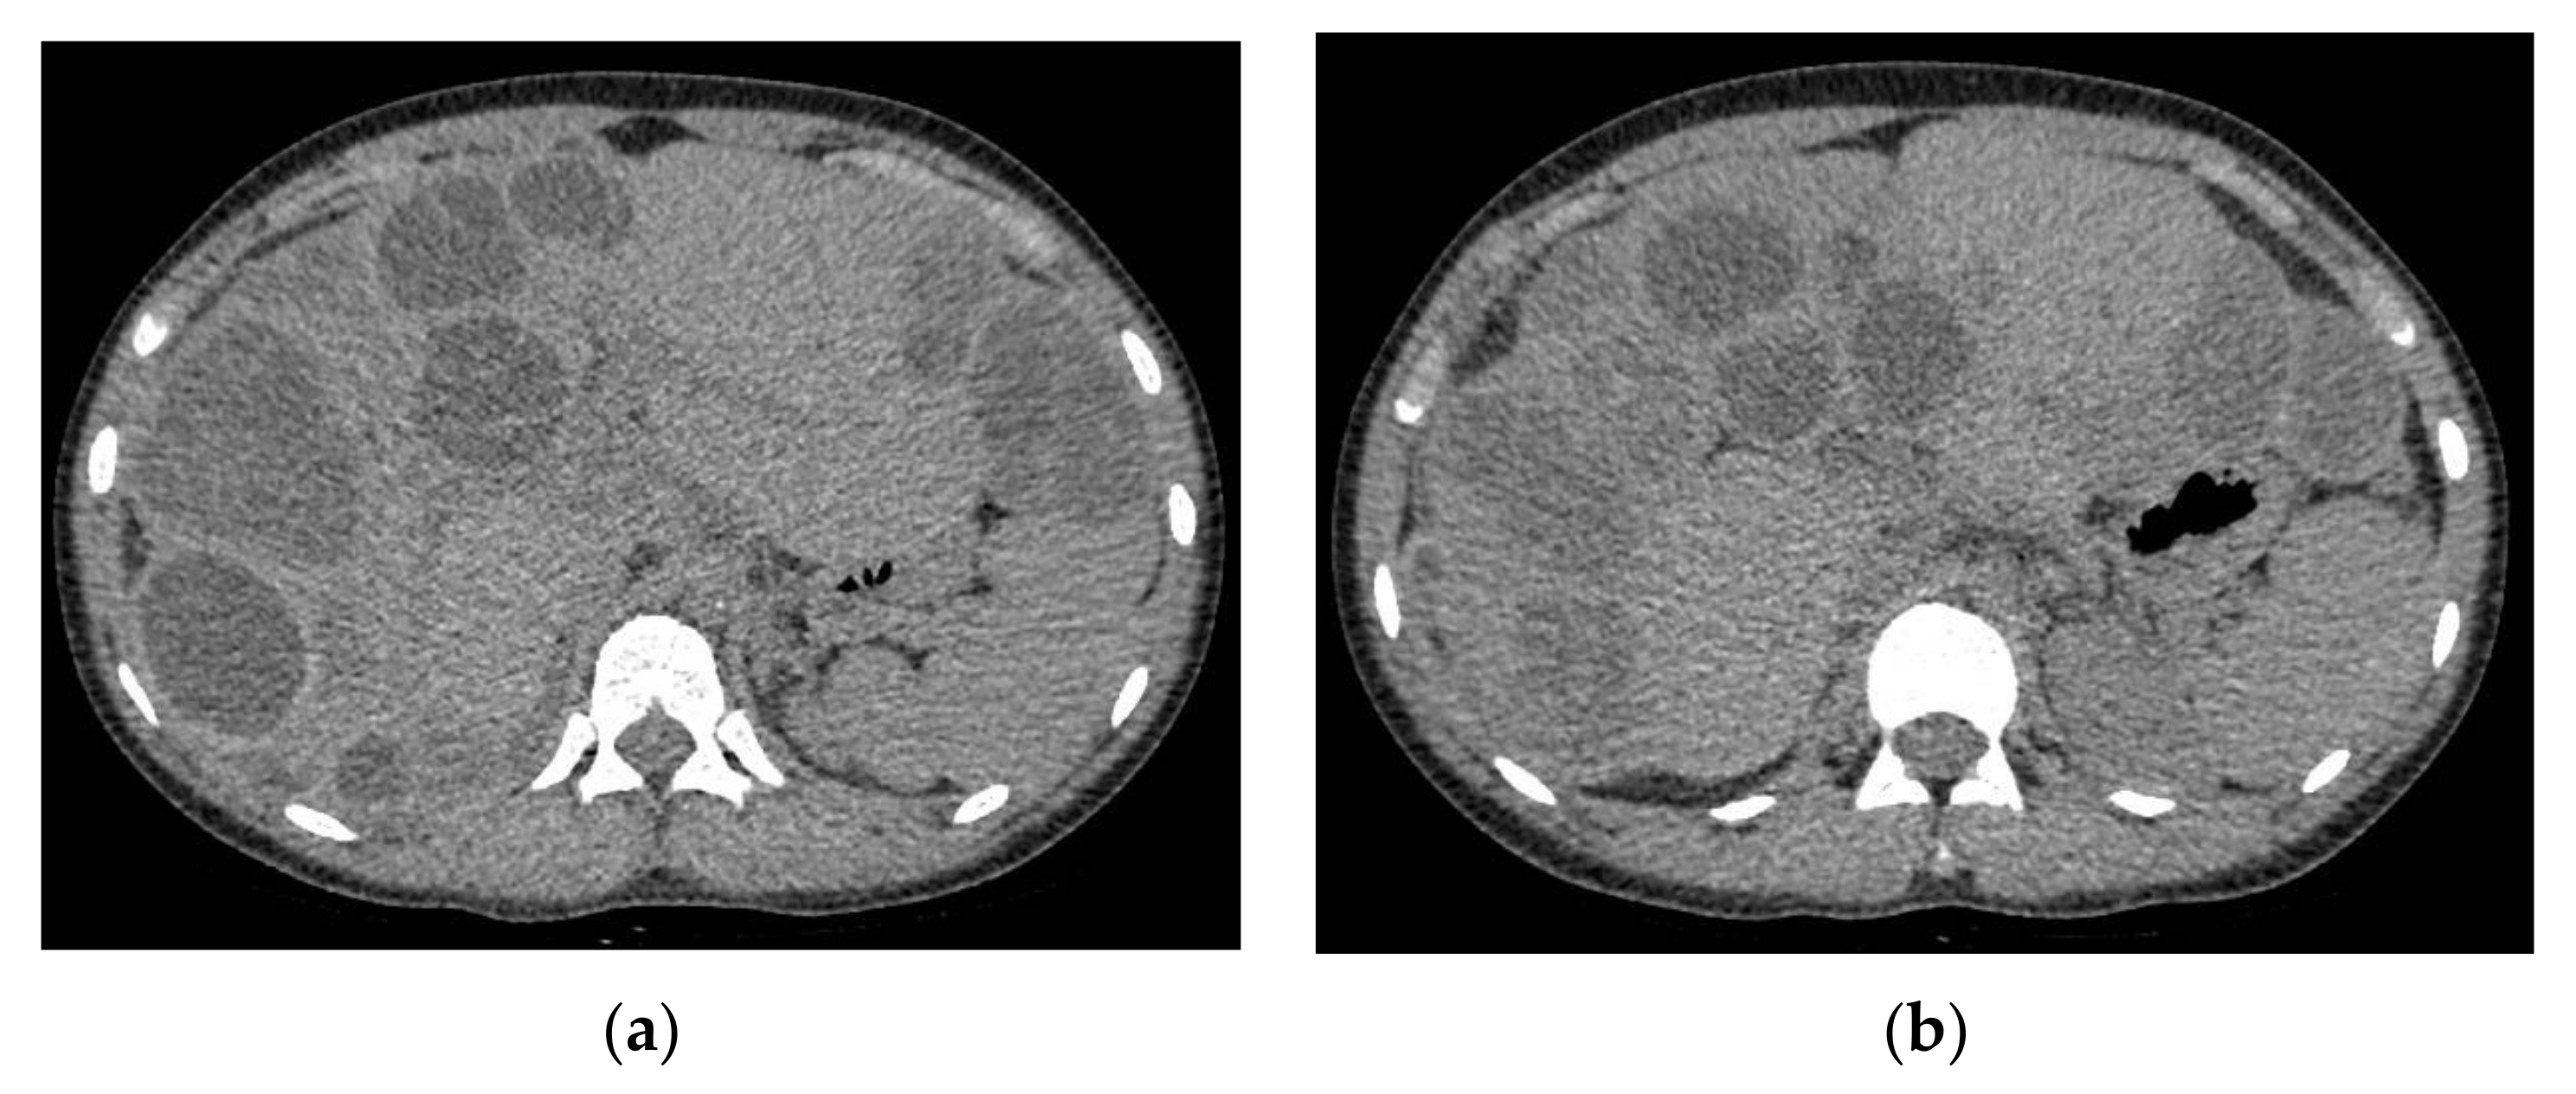

A head computed tomography (CT) Scan with intravenous (IV) contrast (Figure 2 and Figure 3) showed a huge left frontal cyst, with a fine wall and a fine septum inside, minimum peripheral load, left frontal osteolysis, moderate peripheral edema, edematous optic nerves (bilateral secondary papillary edema). Cranio-cerebral magnetic resonance imaging (MRI) examination with contrast (Figure 4) supported the diagnostic suspicion of a cerebral hydatid cyst. Cystic lesions with membranes and daughter cysts are highly probable to be hydatid ones [7]. Based on the morphology classification, this hydatid cyst was a type IIa: a cyst with round daughter cysts at the periphery [8].

The abdominal CT Scan identified important liver regeneration with a dimensional progression of 2 cysts. For these, it is expected that other surgeries will follow (Figure 10).

Figure 10. Abdominal CT scan. (a,b) we can see the areas with viable parenchyma improved compared with the previous abdominal CT Scan.